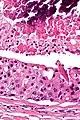

| Low magnification micrograph of a salivary duct carcinoma with characteristic comedonecrosis (left of image) adjacent to normal parotid gland (right of image). H&E stain. | |

Very low mag.